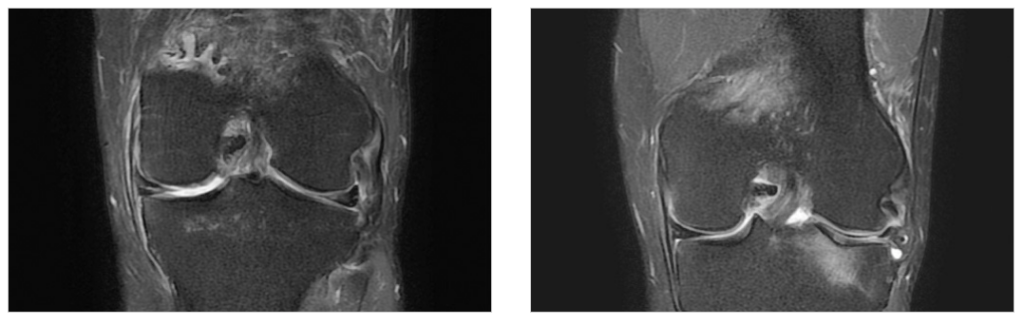

3) MRI 검사

오산무릎관절경수술의 정확한 계획을 위해 MRI는 필수적인 검사입니다. MRI는 연골·인대·반월상연골의 손상을 정밀하게 확인할 수 있는 영상 검사입니다. 동탄시티병원은 3.0T MRI(SIGNA™ Pioneer)와 1.5T MRI 2대를 운영하여 당일 검사가 가능하며, 대기 시간을 줄입니다.

MRI의 장점

- 연골·인대·반월상연골을 직접 확인

- 골수 부종·염증 조직 평가

- 수술 전 정확한 손상 부위·정도 파악

- 방사선 피폭 없음